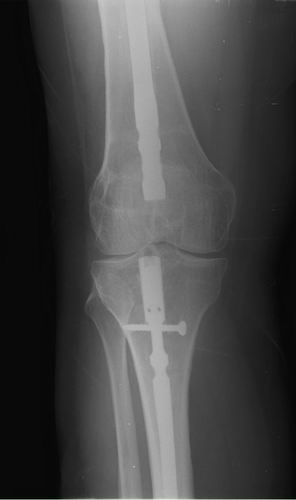

Хочется услышать ваше мнение. Пациентка 48 лет, без вредных привычек, получила свежую травму (с\3 диафиза правого бедра) при падении с лестницы.

Ранее (8 лет назад) была множественная травма, на бедре – перелом с\3, выполнен остеосинтез DFN Synthes (в др. ЛПУ). Перелом диафиза консолидировался очень медленно, от реостеосинтеза категорически отказывалась, в результате к 2 годам наступило сращение. Беспокоили боли при нагрузке, на рентгенограммах – зона разрежения вокруг кончика (проксимального) стержня и проксимальных винтов, согласилась лишь на удаление дистальных винтов для динамизации стержня. Пациентка пропала из поля зрения. Затем спустя 2 года при падении получает чрезвертельный перелом, выполнен остеосинтез бедренным винтом ( DHS ).

Планирую удаление имплантов (кроме проволоки), рассверливание костно-мозгового канала (сейчас стоит гвоздь 10 мм, попытаюсь рассверлить до 14-15 диаметра, чтобы поставить 12 мм или 13 мм гвоздь), внутрикостный остеосинтез блокированным стержнем (динамически).